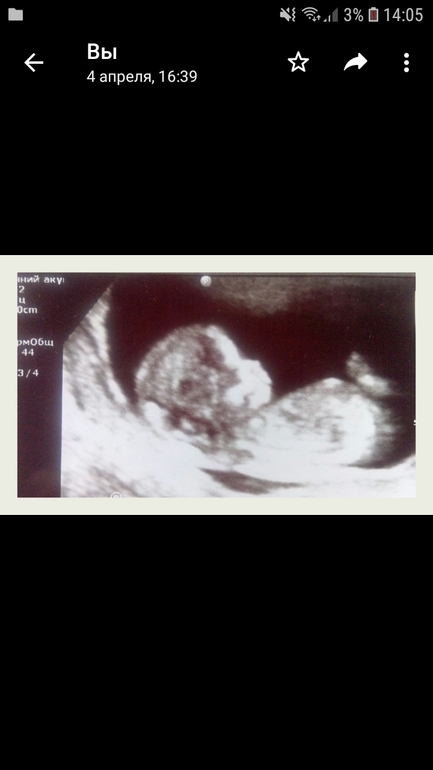

УЗИ в 12 недель

Ну насчёт носика я не знаю, а вот ножки и животик маленькие всего на 11,2 нед. хотя на момент УЗИ по месячным уже 12,4нед.

Такая же компактная на фото.и ктр был 55.сейчас бер 60 ктр.

По половому бугорку - девочка))) пусть так и будет!🙏🏻

Моя узистка насчёт пола по чсс сказала, что это ерунда и что лично она на это не смотрит, так как были и с высоким чсс мальчики, и с низким девочки. На вашем фото похоже девочка)